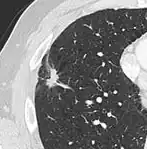

Lung nodule abutting a pulmonary cyst.[9]

• A lung nodule abutting a pulmonary cyst is a rare finding, yet indicating cancer.[9]